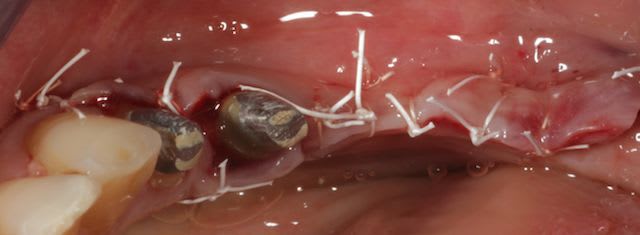

Je prends le train en marche..

Bravo D57 pour ta chirurgie de reconstruction avec le systeme Fast.

mais j'ai quelques remarques:

1. tes vis ne sont pas positionnées comme il faut.

2. tes vis sont trop enfouies

3. tes sutures ne sont pas assez profondes. comme je te le disais à l'ADF, tu dois être à au moins 1 cm de la berge.

4. Donc, je peux te le dire d'avance: le résultat sera moyen. Je t'avais proposé de préparer ensemble le protocole chirrugical. dommmage.